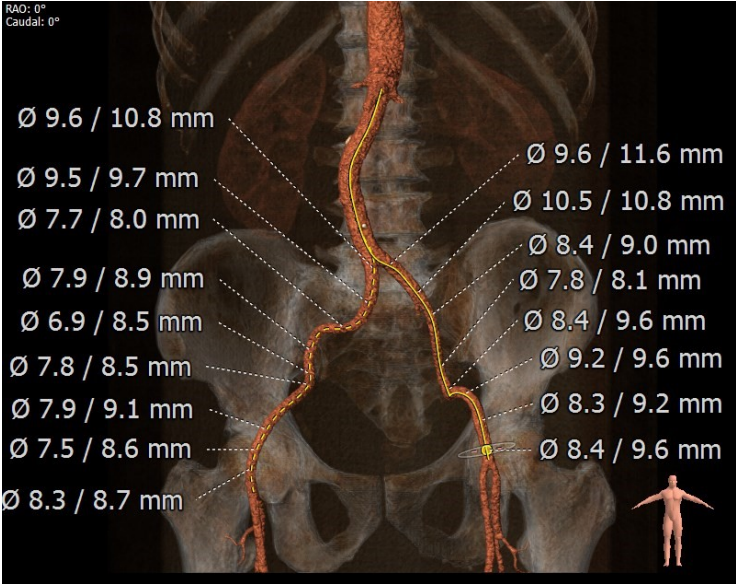

入路分析

术前陈晓敏教授带领团队对这位患者进行了详细的分析,从CT分析结果显示,患者主动脉瓣为type 0型二叶瓣,瓣环直径为24.4mm,结合患者瓣叶钙化等情况,符合美敦力Evolut PRO 29mm瓣膜选型。经讨论决定以右侧股动脉为主入路,左侧股动脉为辅入路,术中进行23mm球囊预扩张,保证系统顺利跨瓣及释放,并采用世界先进的Cusp Overlap技术植入瓣膜 ,以更精准地释放瓣膜深,减少对患者传导系统的影响。